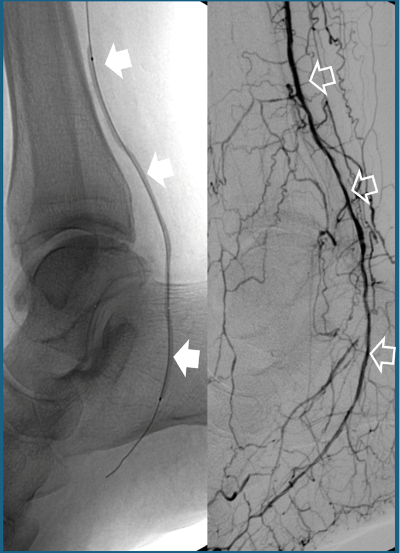

- Angioplastia con stent o sin: mediante un catéter se dilata la arteria bloqueada (Fig.1). Y si esto no es suficiente para mantener el vaso abierto, se coloca un pequeño muelle (stent) que la mantiene abierta

Fig.1. A: Angioplastia con catéter balón (flechas blancas sólidas) de un vaso distal de la pierna ocluido. B: su resultado final con el vaso reabierto (flechas blancas vacías).